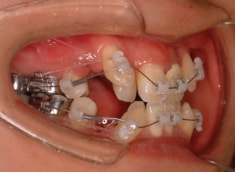

治療開始時

治療開始から約1年後